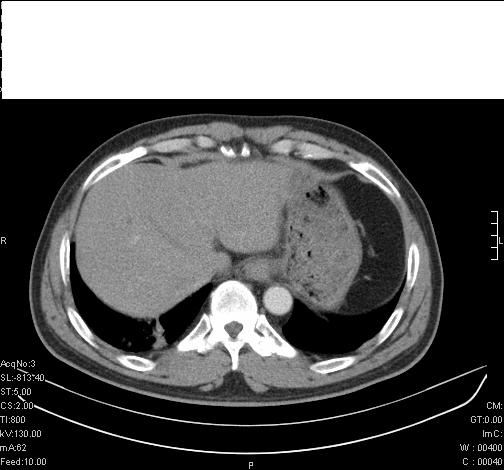

标题: CT6685:右肺阻塞性炎症,增强CT。

前几天,发了患者的平扫片,患者抗炎一周后增强扫描。右中叶病灶吸收明显,但下叶病灶未见明显吸收。右肺门可见结节影,看来凶多吉少

右肺下叶支气管管腔狭窄,管壁增厚,右下肺见斑片状高密度影,考虑右侧肺门中心肺癌伴阻塞性肺炎

右肺下叶散在的斑片状致密影,下叶支气管变窄。考虑:右肺慢性炎症。

右肺下叶支气管壁不规则增厚,右肺下叶有斑片状影分布。考虑右肺中央型肺癌伴右肺下叶阻塞性改变。建议支纤镜检查。平扫比增强较好显示了病变情况。

既然抗炎治疗有效,可继续治疗;右肺下叶支气管管腔狭窄,管壁增厚,右下肺见斑片状高密度影,右侧主支气管后见结节影(淋巴结?),肺癌不能排出。